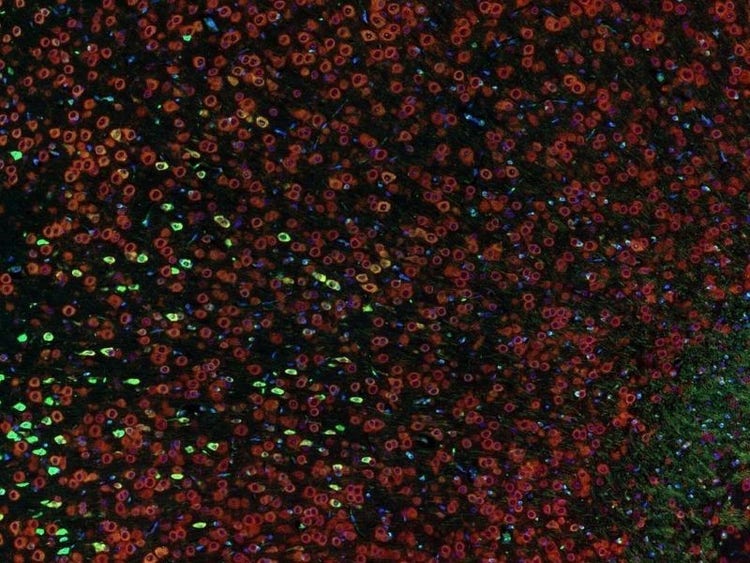

Fluorescence imaging of a mouse brain

尽管每幅图像近看各不相同,但将其拼接在一起则可组成一幅小鼠大脑的荧光图像。

英国科学家乔治·斯托克斯在用紫外线照射矿物萤石时首次观察到了矿物萤石发出的荧光,并创造了“荧光(fluorescence)”这个词。斯托克斯注意到荧光的波长比激发光的波长更长,这种现象现在被称为斯托克斯位移。无论是自然具有荧光的材料(称为原发荧光或自发荧光),亦或是经过有机染料处理后产生荧光的材料(称为次生荧光),荧光显微镜都是研究这些荧光发光材料的最佳工具。